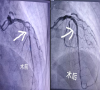

東莞47歲男子胸口痛忍了三天才就診,一查心臟血管堵了三條

47歲的岳先生正值壯年,平時也沒覺得身體有大問題。然而,7月17日晚起,一種揮之不去的疼痛纏上了他——心前區(qū)持續(xù)疼痛。更讓他不安的是,用力咳嗽或者按壓時,這疼痛...